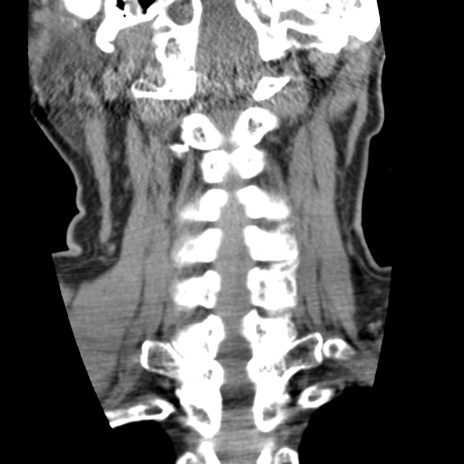

症例50 頚椎CT(冠状断像)

【症例】60歳代女性

【主訴】後頭部〜右後頸部にかけての痛み

【現病歴】本日飲食店でコーヒーを飲んでいたところ、突然後頭部〜右後頸部にかけて痛みが出現し、右上肢の感覚障害を伴ったため救急要請。

【身体所見】脳神経学的に明らかな異常所見を認めず。右上肢に軽度の感覚障害あり。

異常所見と診断は?